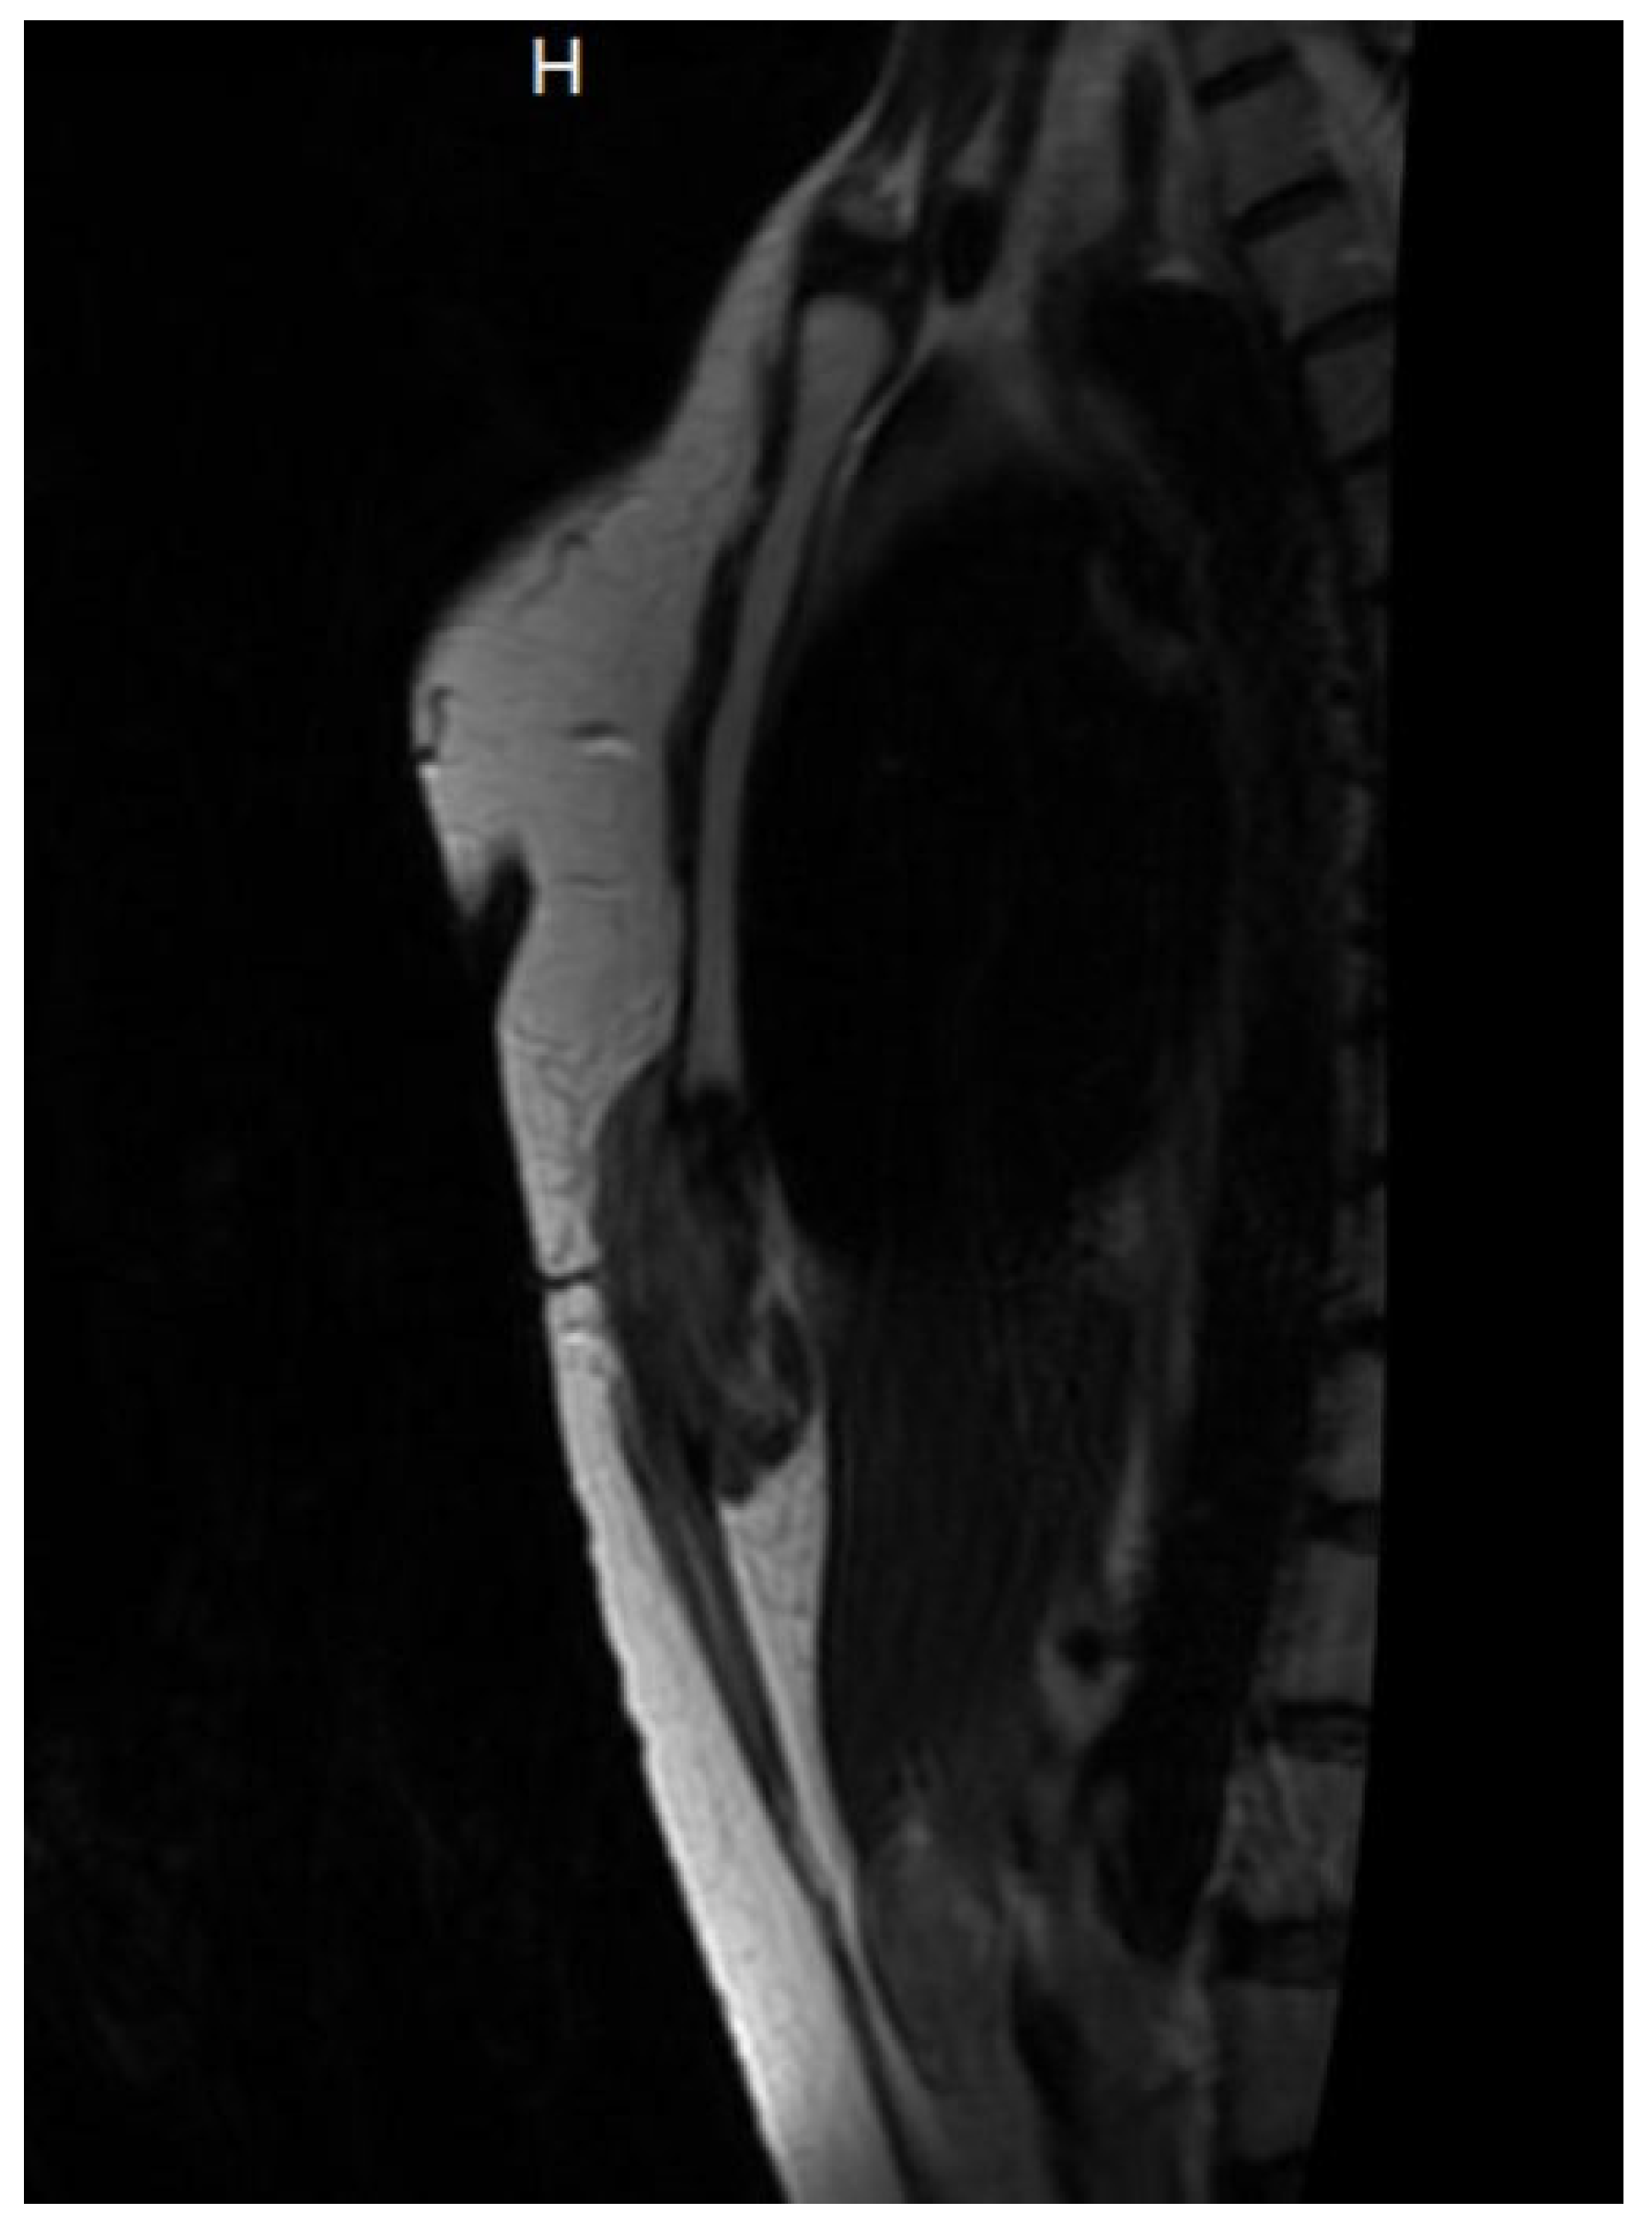

2.1. Initial Diagnostic Workup

3.1. Diagnosis and Imaging Characteristics